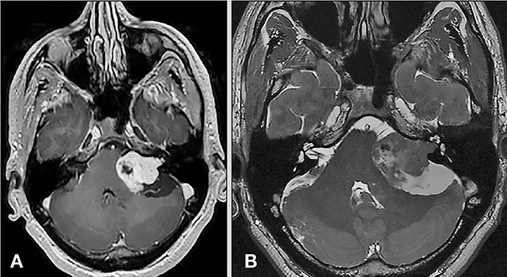

年近花甲的李先生,近年来听力越来越差,以为是年龄大了出现的正常现象,较近常常还出现耳鸣、头晕、头痛等症状,才引起了李先生的重视,于是李先生在医院进行ct检查,才找到了真实的病因。在ct检查的片子上,已经明显可以看到李先生的脑内已经有一个肿块,经过医生确诊,这个肿块是一个听神经瘤,并且已经长到了快三厘米大小,而李先生出现的耳鸣耳背、头痛头晕都是这个“瘤”引起的,需要及时采取治疗。

另外巴特朗菲教授指出,虽然听神经瘤在医学上定性为良性,但对人体也有着影响,需要及时治疗。听神经瘤的早期症状包括逐渐丧失听力和耳鸣,随着肿瘤的生长,平衡问题经常会出现。压迫邻近脑干的较大肿瘤可能影响其他局部颅神经,导致面部无力、麻木和刺痛,受累侧的面部和口腔感觉受损,随着继续不断增大,严重压迫脑干还可能造成患者生命危险。

目前国际上,对于擅长听神经瘤手术的,国际颅底肿瘤手术教授巴特朗菲教授便是其中之一。巴特朗菲教授专注于神经外科,已经具有几十年的经验,每年都进行400台以上的高难度手术,练就了一手神乎其技的手术技术。面对听神经瘤的治疗,只要患者之前没有听力损失,或者肿瘤在3-4厘米以内,巴特朗菲教授都有信心成功手术,并尽可能地保留功能。术后,37%的患者表现出短暂的(轻微)神经功能缺损,其余超过90%的患者,神经功能与术前持平或好转。